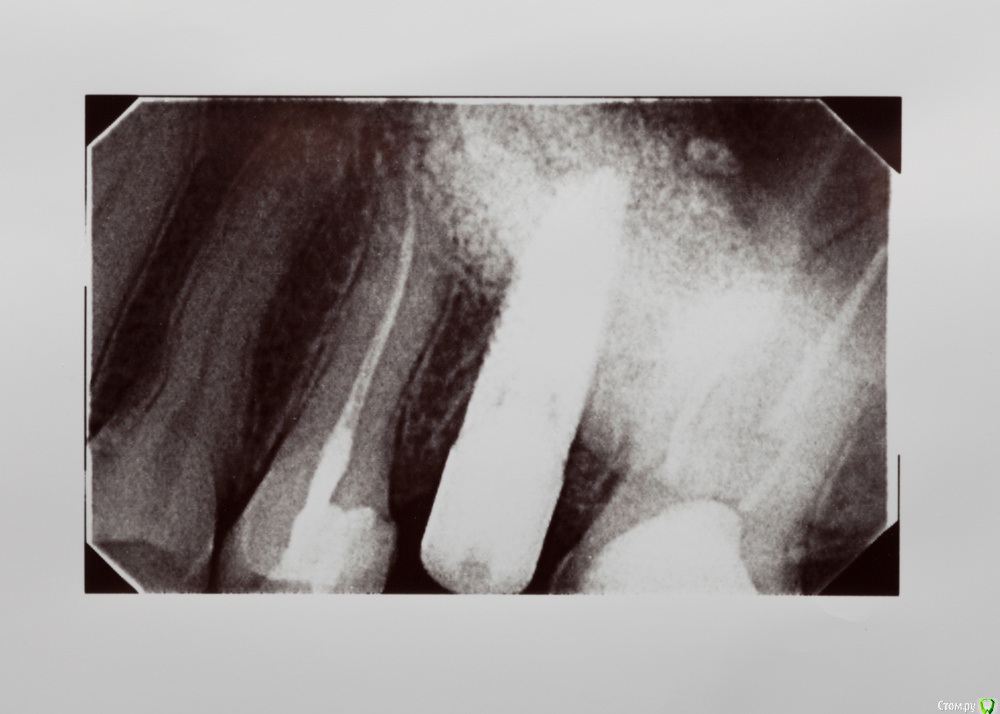

венди Опубликовано 26 января, 2017 Поделиться Опубликовано 26 января, 2017 (изменено) Добрый день! Не знаю в какой раздел будет правильно добавить, т.к. проблема смешанная. Помогите, пожалуйста! 3 месяца мучений. В прошлом году начала заниматься зубами. Был сделан панорамный снимок (прилагаю).В мае в районе отсутствующего 26 был установлен имплант с одновременным открытым синус-лифтингом. Послеоперационный период протекал более-менее нормально. Меня отпустили на пол года. И я стала заниматься остальными зубами. Лечили кариес справа, был удален 46 (резорбация мед. стенки медиального корня с перфорацией). К осени добрались до левой нижней стороны. 26.09. - был залечен кариес в 36 зубе. После этого зуб стал стрелять током при накусывании. Врач решила ещё понаблюдать.19.10. - 37 зуб с гранулемой был распломбирован, врач прошла каналы, заложила кальций. Через 6 дней ещё раз все прочистили, запломбировали каналы полностью, поставили временную пломбу и сказали, что можно протезироваться. Вроде зуб после лечения не беспокоил.01.11. - я пошла на осмотр к хирургу по поводу удаленного 46. Хирург решил раскрыть имплант, т.к. уже время подошло. Сказал всё хорошо прижилось и поставил формирователь десны. С этого дня моя жизнь разделилась на до и после.. Стала болеть вся область вокруг импланта, появилось ощущение мешающего валика под щекой, формирователь утонул в десне, отечность в этой области была. Обобщу и скажу, что после этого формирователь перекручивался еще 3 раза, внутри все промывалось, я принимала антибиотики. Острые ощущения немного ушли, но дискомфорт мешающий нормально жить оставался. По снимку - все отлично, имплант интегрирован (прилагаю). Одновременно с этими манипуляциями с имплантом 36 зуб стал не только бить током, а до него уже нельзя было дотронуться. 18.11 - вскрыли, депульпировали, заложили кальций и через неделю закрыли все постоянной пломбой (снимок прилагаю). Всё это время, впрочем как и сейчас вся левая сторона была охвачена ужасными ощущениями. Распирание, нытье, давящая боль, дискомфорт и днем и ночью. Стала плохо спать. Перед Новым Годом хирург принял решение выкрутить формирователь и посмотреть за динамикой. Мне показалось, что стало немного легче, особенно что касается ощущение валика под щекой. НО все равно с левой стороны мне что-то болит. От области импланта ли это идет или от 36-37 - я не знаю, не могу точно дифференцировать.... т.к. ковырялись везде одновременно и у меня уже все спутано... Никто не может понять, что со мной, т.к. по снимкам и 3Д все отлично. На прошлой неделе придя в очередной раз в клинику - по панорамному снимку и моим жалобам на боли поставили диагноз "дисфункция ВНЧ, артроз ВНЧС слева". При этом я спокойно открываю рот без болей, щелчков и хруста, при жевании тоже ничего не болит. Назначили физио и Аэртал - принимаю больше недели вообще все без изменений... аэртал даже не обезбаливает особо. На данный момент я ощущаю постоянный тупой ноющий тянущий дискомфорт слева. Чувство распирания. Поднимается иногда температура 37-37,1. Плохо сплю, нервничаю, т.к. очень снизилось качество жизни. Помогите, пожалуйста, разобраться. На что бить, если по снимками как бы все хорошо?! Имплант, 36, 37, сустав?? Все началось с раскрытия имланта. До этого я жила обычной жизнью. Есть 3Д декабрьские. Если кто-то захочет посмотреть я добавлю. Спасибо! Изменено 26 января, 2017 пользователем венди Ссылка на комментарий